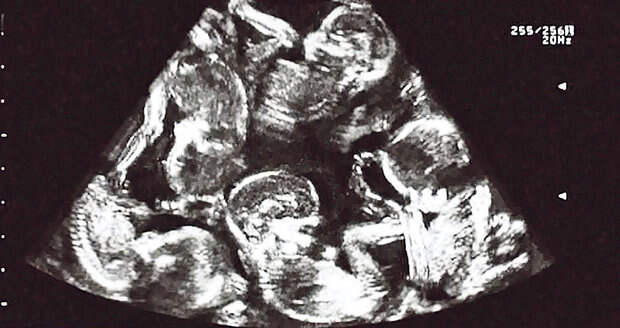

Со смешанными эмоциями, беспокойством и нервозностью, врач решил еще раз продемонстрировать им результаты УЗИ. Когда Александра взглянула на них, она громко закричала.

Новое заключение медиков — в утробе матери находится тройня!

Но и этот вывод вскоре был разрушен. После детального изучения и повторного осмотра, врачи сообщили, что семье стоит ожидать рождение четырех детей!

Это был настоящий шок, два дня назад они ждали двойню, а теперь уже четверых! Но далее случилось нечто невероятное! Очередная диагностика…УЗИ….пять…целых пять детей было в животе Александры!